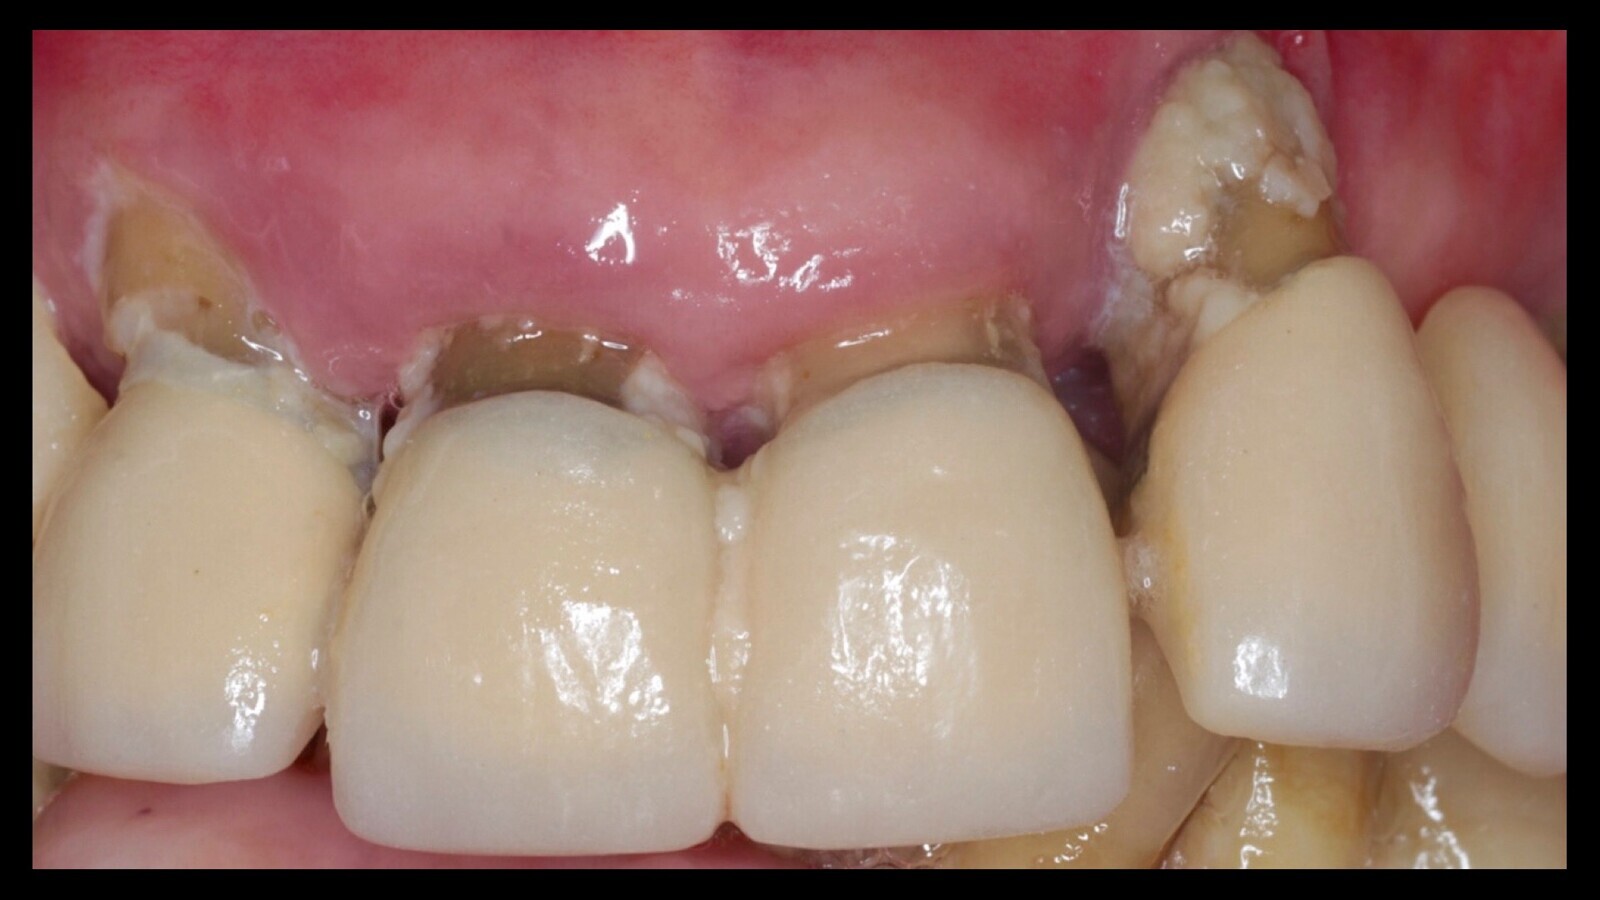

Estado de la dentadura de un paciente bajo tratamiento crónico con fluoxetina y afectado también por xerostomía.

Iván Herrera Ustariz